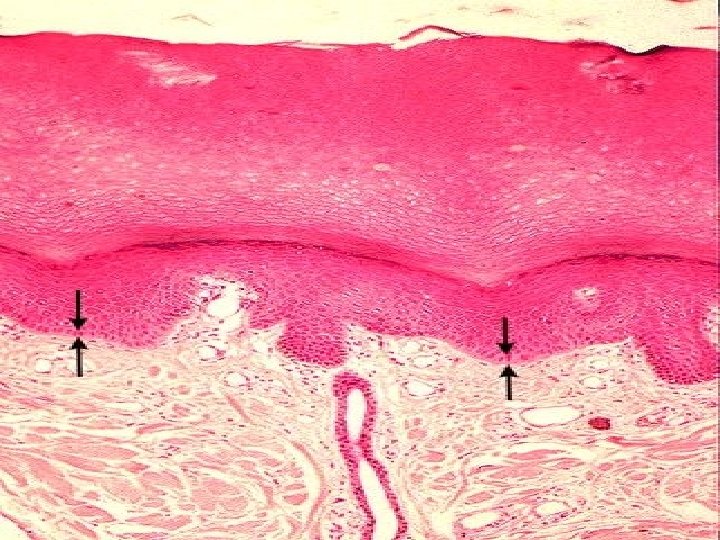

TYPES OF SKIN • Thin skin – covers all parts of the body except for the palms and palmar surfaces of the digits and toes. – lacks epidermal ridges – has a sparser distribution of sensory receptors than thick skin. • Thick skin (0. 6 to 4. 5 mm) – covers the palms, palmar surfaces of the digits, and soles – features a stratum lucidum and thick epidermal ridges – lacks hair follicles, arrector pili muscles, and sebaceous glands, and has more sweat glands than thin skin.

Specific Layer of the Epidermis Stratum Lucidum: • Observed only in nonhairy or thick skin. Several layers of dead cells with indistinct boundaries Stratum Corneum: • Composed of 25 or more layers of dead squamous cells still joined by desmosomes. Eventually desmosomes break and cells flake off in a process called desquamation